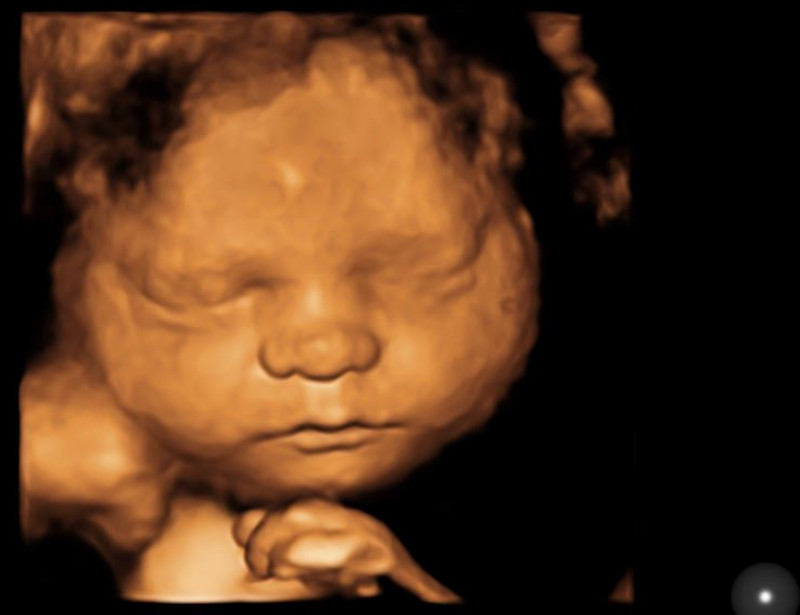

3D ultrasound takes imaging a step further by creating a three-dimensional representation of the fetus. Expectant parents often appreciate 3D images for their ability to reveal facial features and other details, making it a popular choice for keepsake photos. 4D introduces the element of motion to 3D. Expectant parents can see their baby moving.

HD Live ultrasound provides high-definition, real-time images that offer a stunningly clear view of the fetus. With enhanced detail and depth perception, HD Live ultrasound allows parents to see their baby moving and even making facial expressions. This immersive experience can create a deeper emotional connection between parents and their unborn child.